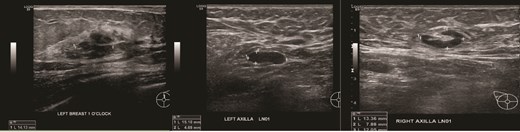

(Left, middle) Ultrasound images of the right breast irregular spiculated hypoechoic mass with ill-defined margins, associated with a dilated duct 3 mm; (Right) Ultrasound image of the enlarged axillary lymph node.

(Left) Ultrasound image of the left breast hypoechoic lesion; (Right) Ultrasound image of one of several enlarged lymph nodes with effacement of fatty hilum.